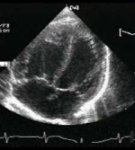

Szívultrahangos (Echokardiográfia) vizsgálat kapcsán a Medconnexus Gyógyászati Központban a szív, nagyerek, billentyűk funkció közbeni vizsgálatát végezzük rutinszerűen.

Az ultrahangos vizsgálat sajátosságából fakadóan az emberi szervezetre teljesen ártalmatlan, így az észlelt eltérések tetszőleges számú esetben kontrollálhatóak, az esetleges visszafejlődés, vagy progresszió nyomon követhető anélkül, hogy a vizsgálat bármilyen formában is megterhelő lenne.